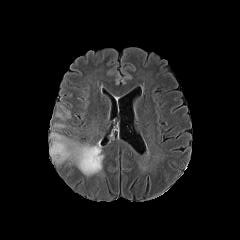

Starting from the baseline GAN model, which consists of the 𝒢A2Nsubscript𝒢A2N\mathcal{G}_{\rm{A2N}} generator without shortcut and AM loss and cycle consistency, we conduct the following ablation study to validate the cycle consistency, AM loss and shortcut.

IV-B1 Evaluation of the cycle consistency

We first conduct experiments to compare the baseline GAN [8] to the same model, but with the abnormality or normality synthesis consistency penalty terms (GAN+AC and GAN+NC). In Figure 5, we show generated (i.e., fake) healthy-looking MRI produced by GAN, GAN+AC and GAN+NC. We observe that model collapse occurs in GAN and GAN+NC where the generator networks have converged to a bad local optimal solution. GAN+AC produces more meaningful image structures, however it still suffers severe artifacts due to the lack of optimizing constraints. We compare the above models with CycleGAN as a baseline state-of-the-art model for unsupervised image-to-image translation [35]. The cycle consistency term reduces the artifacts by modifying the search space. However, the gray scale shift shows some bias.

IV-B2 Evaluation of the shortcut and anomaly mask

The global shortcut connection can simplify the function mapping by forcing the generator 𝒢A2Nsubscript𝒢A2N\mathcal{G}_{\rm{A2N}} to focus on the lesion region. We compare with CycleGAN [35] and CycleGAN with a shortcut connection (CycleGAN+shortcut). The difference between CycleGAN+shortcut and our ANT-GAN is the inclusion of the anomaly mask penalty term.

In Figure 5, we observe that the generator can better detect, remove and inpaint the tumor regions without impacting the non-tumor regions by using the proposed global skip connection. However, as shown by the zoomed-in regions, CycleGAN+shortcut still performs less satisfactorily than ANT-GAN in terms of some important details of the healthy regions of the lesion-containing MRI. This is because ANT-GAN contains the anomaly mask term, which forces the generator 𝒢A2Nsubscript𝒢A2N\mathcal{G}_{\rm{A2N}} to leave healthy portions of an MRI unchanged and only detect and modify lesions. Both CycleGAN and CycleGAN+shortcut do not have this feature since they have different motivation in their design. Though based on the GAN, ANT-GAN is more motivated by image restoration than image generation.